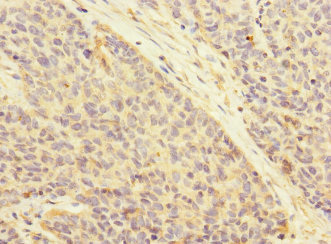

ATRN Antibody - N-terminal region (OAAB18786)

- Product NameATRN Antibody - N-terminal region (OAAB18786)